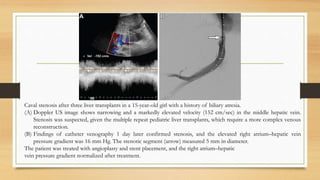

Caval stenosis after three liver transplants in a 15-year-old girl with a history of biliary atresia.

(A) Doppler US image shows narrowing and a markedly elevated velocity (152 cm/sec) in the middle hepatic vein.

Stenosis was suspected, given the multiple repeat pediatric liver transplants, which require a more complex venous

(B) Findings of catheter venography 1 day later confirmed stenosis, and the elevated right atrium–hepatic vein

pressure gradient was 16 mm Hg. The stenotic segment (arrow) measured 5 mm in diameter.

The patient was treated with angioplasty and stent placement, and the right atrium–hepatic

vein pressure gradient normalized after treatment.